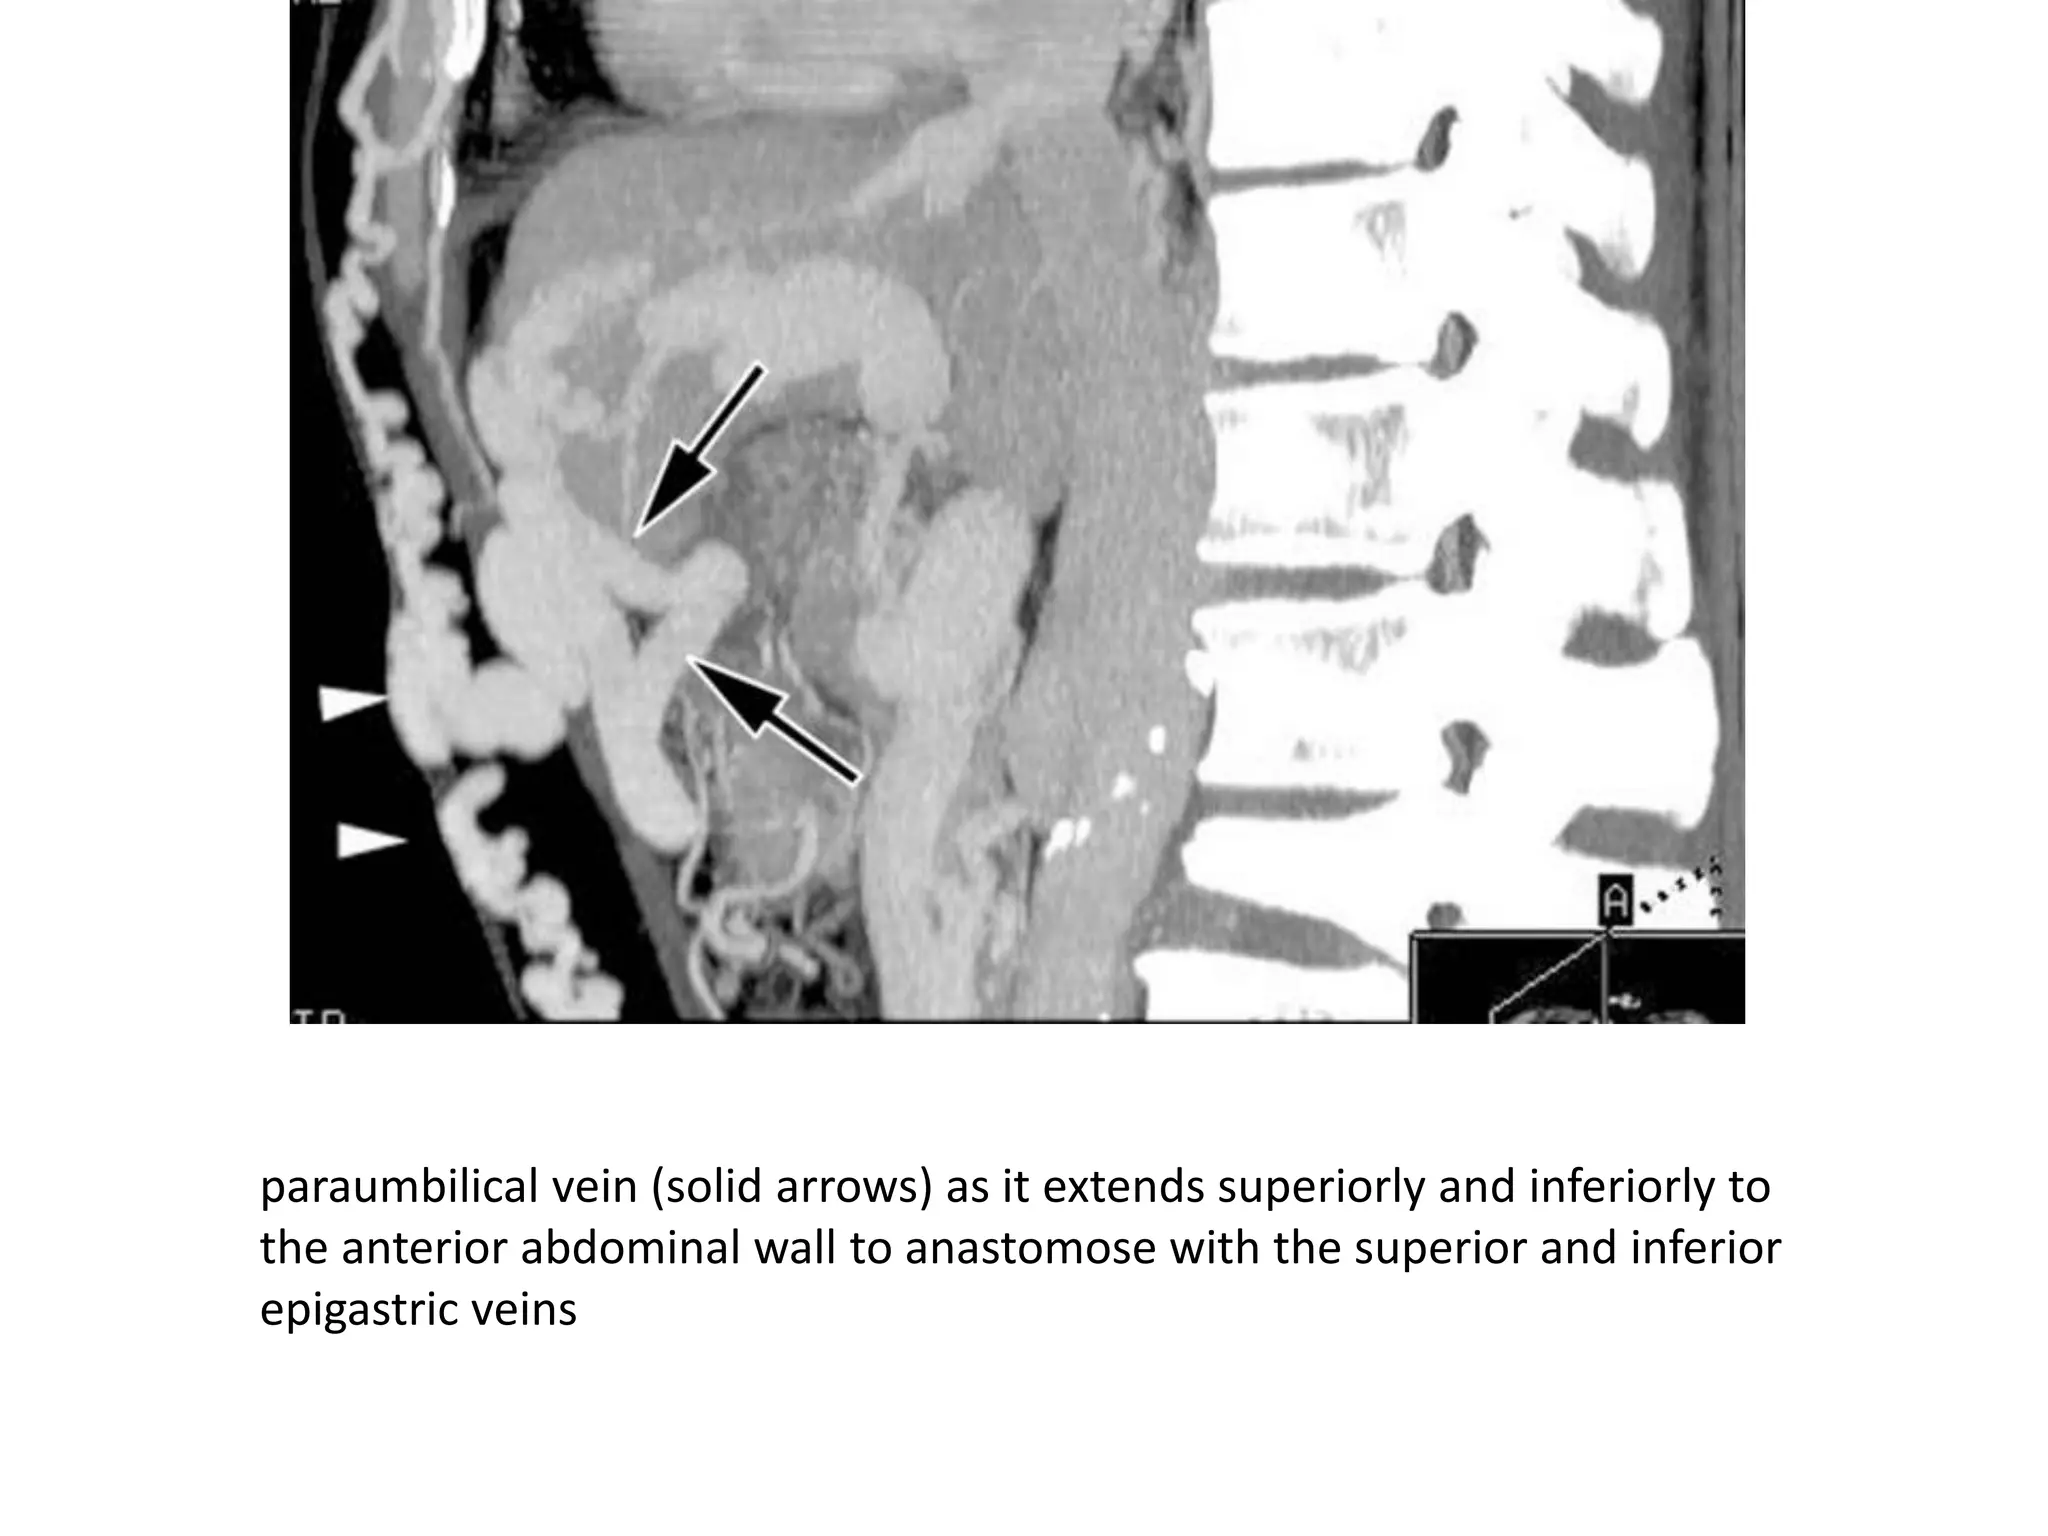

paraumbilical vein (solid arrows) as it extends superiorly and inferiorly to

the anterior abdominal wall to anastomose with the superior and inferior

epigastric veins